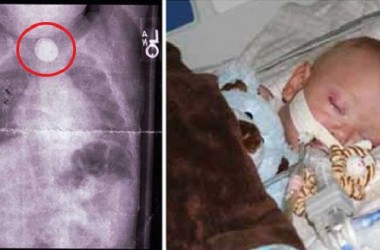

Pero no todo fue de color de rosa… Poco tiempo después, la historia puso a la familia ante un reto insólito: a los cuatro años, Angélica tuvo una terrible doble neumonía y sus riñones dejaron de funcionar. Durante 18 meses, la niña tuvo que someterse a diálisis. Su madre Eva tomó la decisión donar un riñón, para salvar la vida de su hija, y pr suerte, la operación fue todo un éxito.